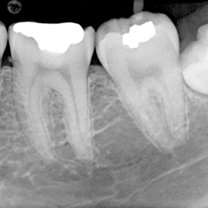

x-rays are taken for the affected tooth and seen for any periapical infection

Root canal treatment is one of the least risky treatment with negligible complications. Root canal failure or re-infection can occur after some years of root canal treatment. This happens if filling or crown over the tooth which is root canal treated is not good or root canal filling is not sufficient. Sometimes root canal file can break while doing the procedure. Then we have to either take the broken file out of the tooth or if not possible then we have to bypass the file and continue with root canal.